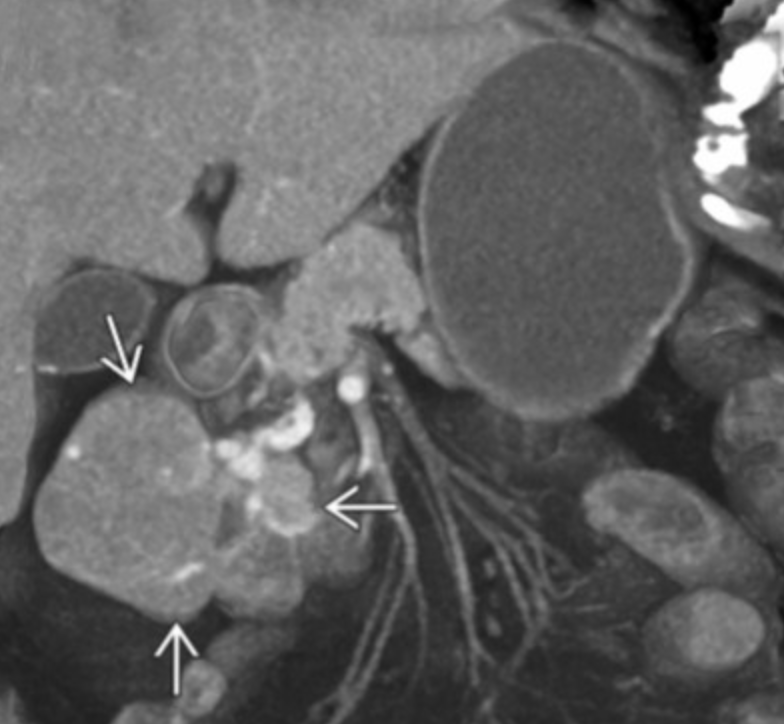

GIST

• Exophytic mass arising from bowel wall

• Central necrosis

• Can result in intraluminal gas and contrast entering the mass which can resemble lymphoma or bowel aneurysm